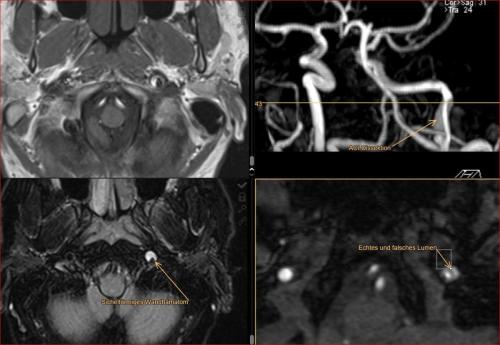

Aneurysma re. 7 mm Darstellung in einer DSA (digitalen Subtraktionsangiographie) links nur ein 2 mm „Baby-Aneurysma“ Im MRT war zuvor das linke Aneurysma aufgefallen, die Auflösung einer DSA ist technisch im MRT nicht erzielbar, beide A. liegen in der ACM Bifurkation jeweils, das re. Aneurysma wurde erfolgreich operiert, das linke Aneurysma wird kontrolliert.